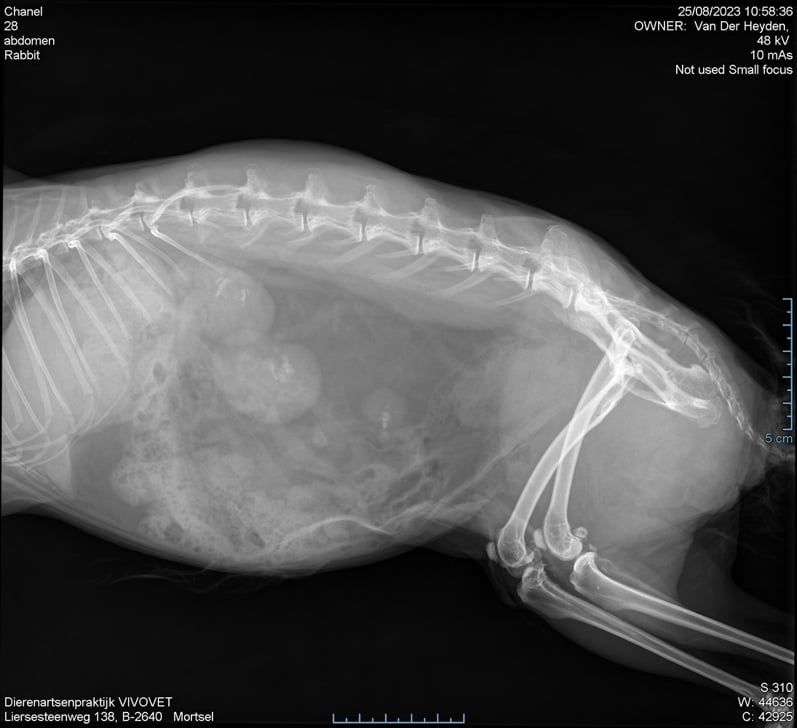

Met behulp van de RX opname was de diagnose snel gesteld. Er zat een grote blaassteen die zorgde voor veel ongemak en pijn.

De blaassteen werd chirurgisch verwijderd via een incisie in de blaas. De steen was bijna even groot als een €2-muntstuk.

Na de operatie werd er nog een RX opname gemaakt om te kijken of alles uit de blaas werd verwijderd. Alles zag er goed uit. Er werden geen restjes van de steen opgemerkt op de RX foto.